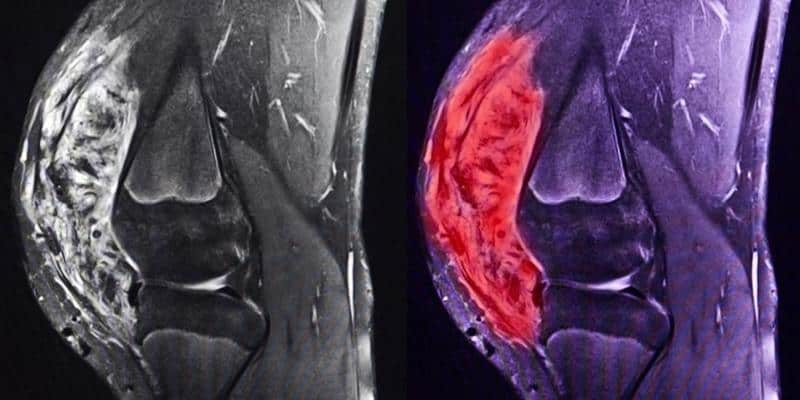

Sarkoma juga dapat dideteksi melalui pemeriksaan medis secara rutin. Kadang seseorang bisa terdeteksi mengidap kanker ini saat menjalani pemeriksaan untuk alasan kesehatan lain, misalnya untuk masalah hematoma (memar/lebam), cedera, tumor jinak (lipoma, fibroma, dll), kista, dan lain sebagainya.